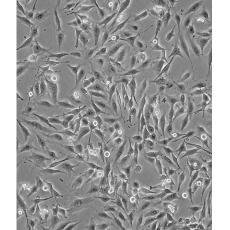

MDA-MB-435S

中文名稱 人乳腺導管癌細胞

組織來源 previously described as: mammary gland/breast; derived from metastatic site: pleural effusion

細胞種屬 Homo sapiens, human

生長特性 adherent

培養基 DMEM+0.01mg/ml bovine Insulin+0.01mg/ml Glutathione+10% FBS+1% P/S

形態特征 spindle shaped

細胞描述 MDA-MB-435S是一種紡錘形的細胞,1976年由其親本(435)中篩選得到。435是從31歲的轉移性乳腺導管腺癌女性患者胸水中分離得到。當用熒光染料對微管蛋白進行染色時親本細胞顯現散布特征(II型)。最近通過cDNA陣列研究表明,親本(MDA-MB-435)可歸入黑素瘤起源。